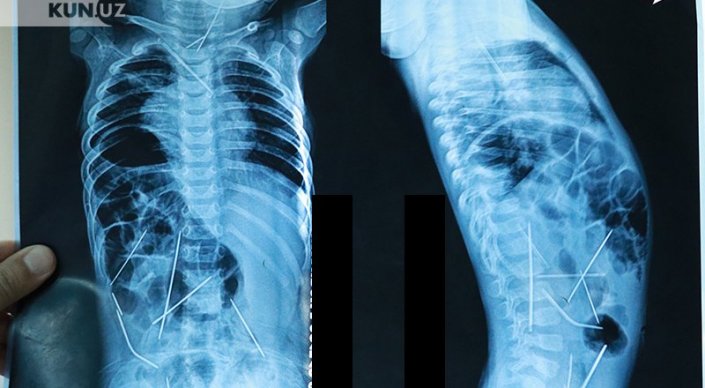

Ташкентские врачи показали ребенка, в теле которого нашли 16 иголок Кадр из видео

Ташкентские врачи показали годовалого мальчика, в теле которого было найдено 16 швейных иголок, сообщают "Новости Узбекистана". По их словам, сейчас его состояние оценивается как стабильное.

"При поступлении состояние ребенка оценивалось как крайне тяжелое. Это объяснялось совокупностью множества патологий: двусторонняя цветущая пневмония, абсцесс в области шеи, множественные инородные тела в грудной клетке, шее, брюшной полости, сказалась и многочасовая операция по извлечению игл", - рассказал профессор, доктор медицинских наук Хабибулло Акилов.

Напомним, маленький Азизбек Абдумаджидов поступил в Республиканский научный центр экстренной медпомощи в середине января с 16 иглами в теле. 13 иголок были удалены в ходе девятичасовой операции, три - до сих пор остаются, но, по уверению медиков, угрозы для жизни малыша не представляют, и их можно извлечь позже.

"Сегодня состояние ребенка с положительной динамикой. Сейчас он на самостоятельном дыхании, аппарат искусственной вентиляции легких работает только во вспомогательном режиме, температура нормализовалась, все анализы нормализовались. Ребенок в полном сознании. До удовлетворительного состояния, конечно, еще далеко. Но улучшения нас обнадеживают", - поделился хирург.